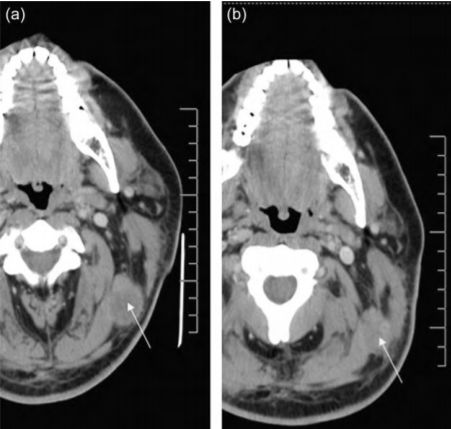

2008年,美国拉什大学医学中心的科研人员将外源扩增的NK异体细胞注入到黑色素瘤患者体内,结果发现,注入注入NK细胞后,该患者左上颈部肿瘤的体积明显降低(从3.15 cm×2.54 cm减小至2.46 cm× 1.76 cm)。同时,该治疗也为外源扩增的NK异体细胞是否可以大规模应用于治疗黑色素瘤提供了一定的理论依据。

△ NK细胞治疗前后对比图